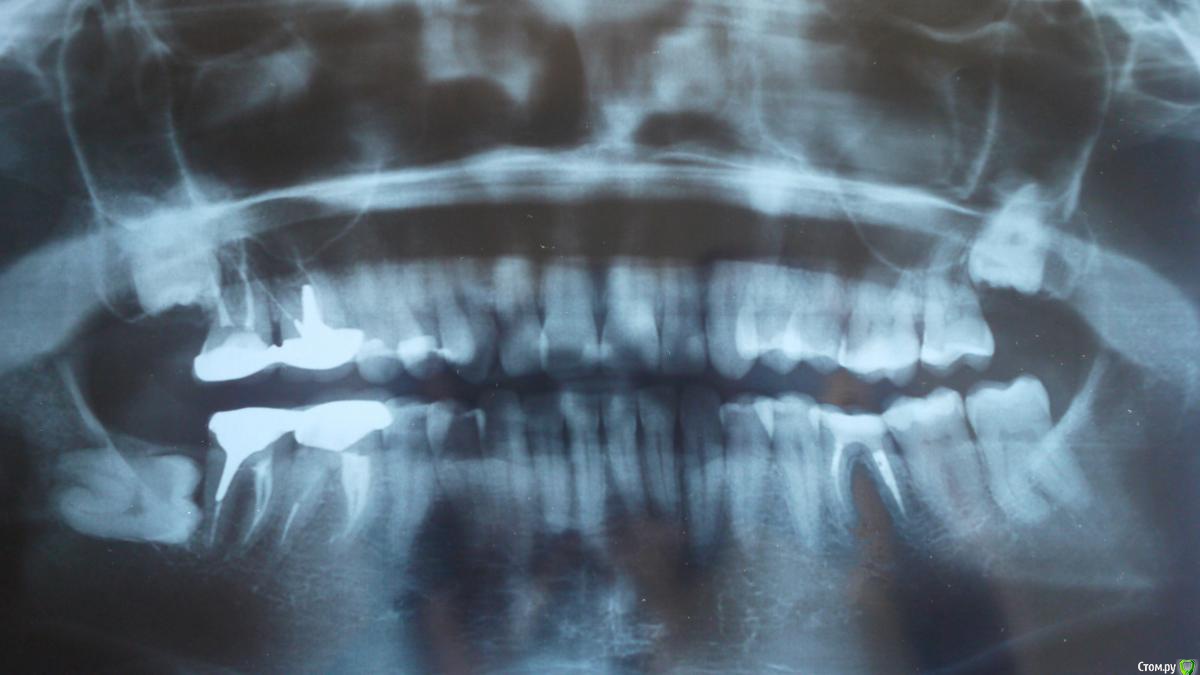

Евгения Shinkar Опубликовано 24 июня, 2018 Поделиться Опубликовано 24 июня, 2018 (изменено) Добрый день!Ситуция: неделю назад начали беспокоить боли в районе десны под левой 6-ой при пережевывании жесткой пищи. Зуб на удаление. Но 28 июня предстоит отъезд на целый месяц в уральскую глубинку, квалифицинованная медицинская помощь будет труднодоступна. В первой клинике хирург сказал удалять немедленно. Во второй - ни в коем случае, только по возвращению.Вопросы:1. Есть ли необходимость в немедленном удалении? (при жевании боль умеренная, думаю месяц смогу прожить с этим)2. После удаления и установки импланта, что обычно делают с антогонистом? Он сильно выдвинут, возможно сохранение зуба? Изменено 24 июня, 2018 пользователем Евгения Shinkar Ссылка на комментарий